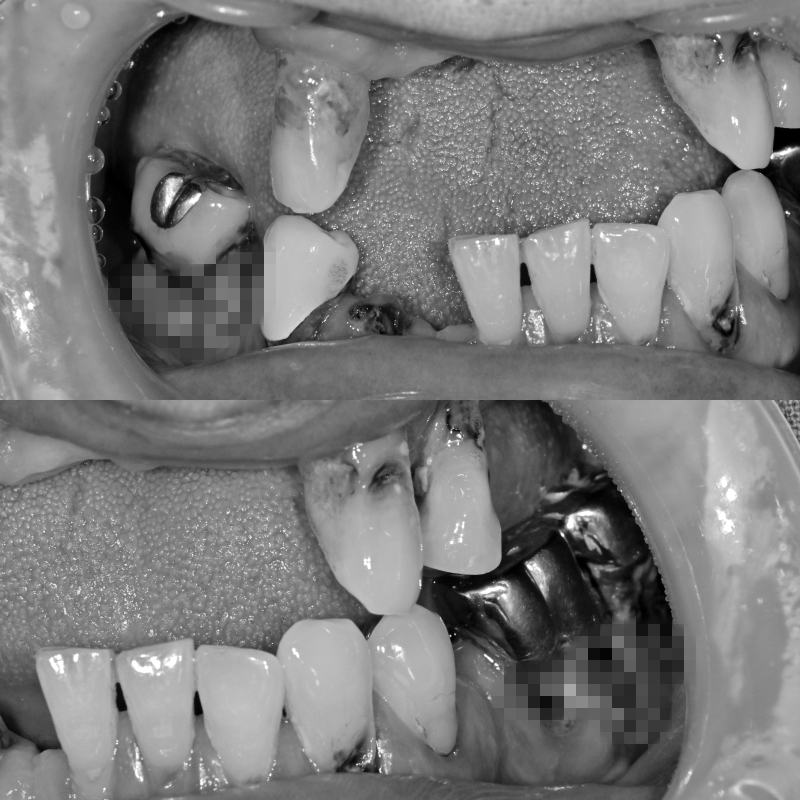

초진 구내 사진입니다.

다수의 상실치아와 치주염에 의해 치아 뿌리가 모두 노출되어 발치가 불가피한 상황이었습니다.